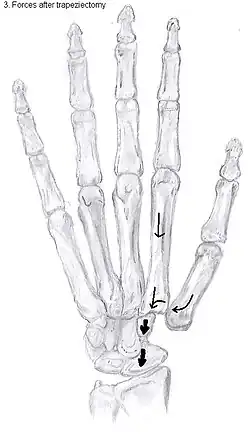

Showing the forces after trapeziectomy

In one randomized trial comparing trapeziectomy alone with trapeziectomy with ligament reconstruction and trapeziectomy with ligament reconstruction and tendon interposition, patients evaluated 5 to 18 years after surgery had similar pain intensity, grip strength and key and tip pinch strengths after each procedure.[29] Trapeziectomy alone is associated with fewer complications than the other procedures.